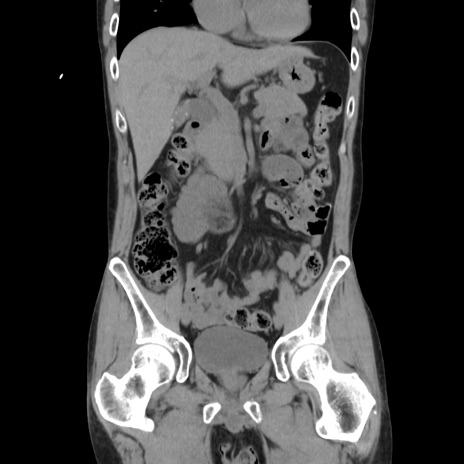

症例37(冠状断像)

【症例】40歳代 男性

【主訴】腹痛

【現病歴】4時間ほど前に電車に乗車中に臍部上より腹痛出現。徐々に増悪し起立困難となり、救急外来受診。生ものは数日食べていない。今朝お雑煮を食べた。

【身体所見】BT 36.8℃、BP 117/84mmHg、HR 91/min、SpO2 97%、苦悶様、腹部:臍上部広範囲圧痛あり、反跳痛±

【データ】WBC 8100、CRP 0.03